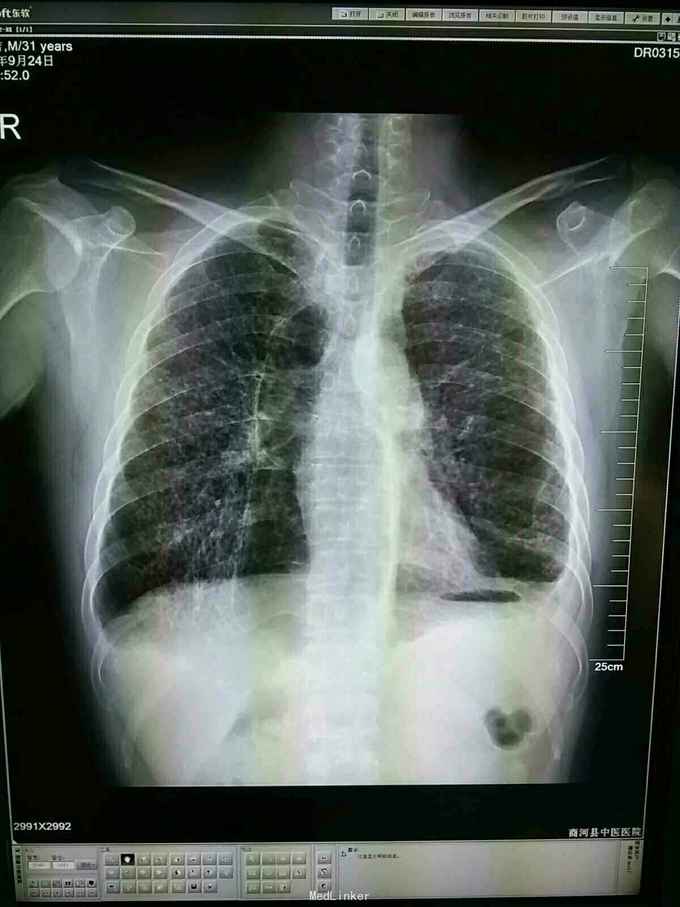

肺大泡

肺气肿

慢性咳嗽,咳痰3年,近日来胸闷,逐渐加重。

双肺过清音,白细胞正常。

肺气肿,纤维化,肺大泡形成。

31岁年青人,慢性病史,肺纹理纤细紊乱,有网挌状改变,肺大泡形成。应进一步检查除外尘肺。